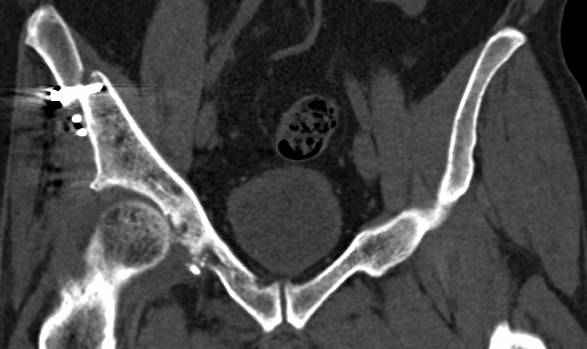

>Вопрос к знатокам: Так что это?

высылаю дополнительно сканы.

итак, второй вариант: высокий двухколонный с вовлечением КПС... Ни одно из основных повреждений не репонировано, кроме задней стенки. Скорее всего попытка реконструкции вертлуги сейчас будет очень травматичной и не очень эфективной, т.е. вероятный риск более значим, чем ожидаемая польза... Лучше подождать, и потом сразу эндопротез

подождать сколько, чего? такая дыра в задней колонне не закроется никогда.

потом эндопротез какой? в такой ситуации приходит на ум Burch-Schneider cage, в 35 лет, дальше что делать?